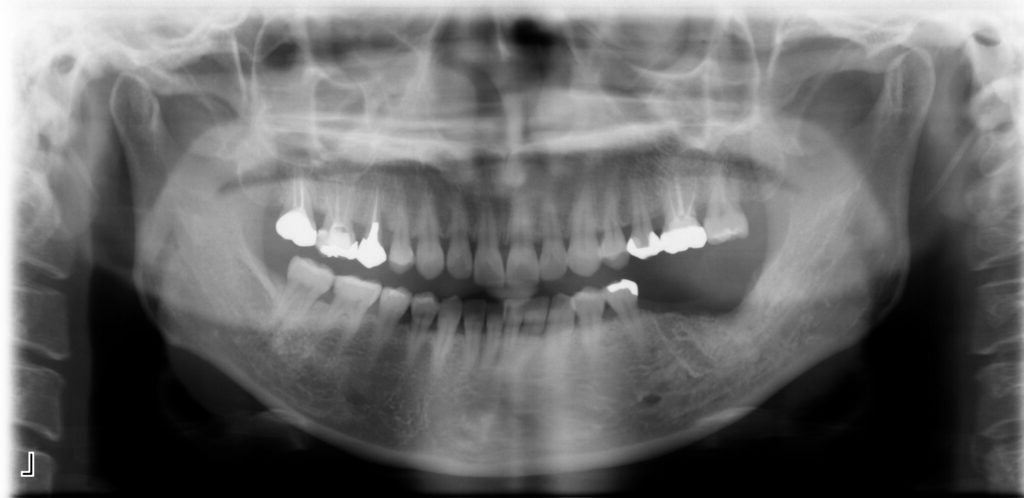

Before

After

治療内容

インプラント2本・骨造成併用

治療期間・回数

約4ヶ月・約4回

費用

880,000円

治療のリスク

外科手術が必要になるため、患者様に体力的な負担がかかる。